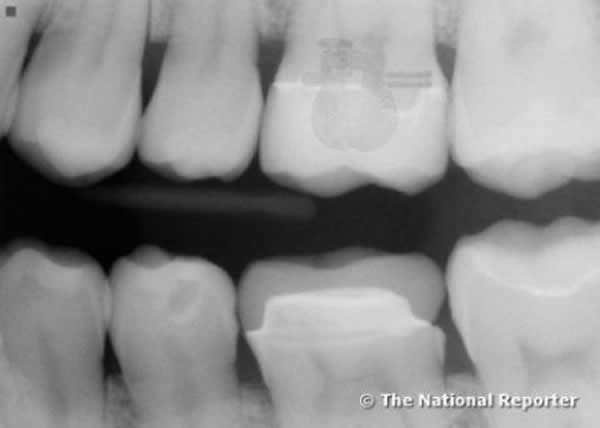

年满六十七的沃利.汉森(Wally Hanson)是一位美国奥尔巴尼的退休警官。他遇上了一件极其奇怪的事:他在做牙齿年检时,发现牙内莫名地出现了一个神秘的金属物体。最后经过FBI测定,那是一个信号发收器。

汉森表示自己竟然完全不知情。牙医弗雷德.沃灵顿证实,1年前照的X光片上并没有出现这个东西,也没有任何的痕迹表明有东西植入,但它就这么突然地出现了。